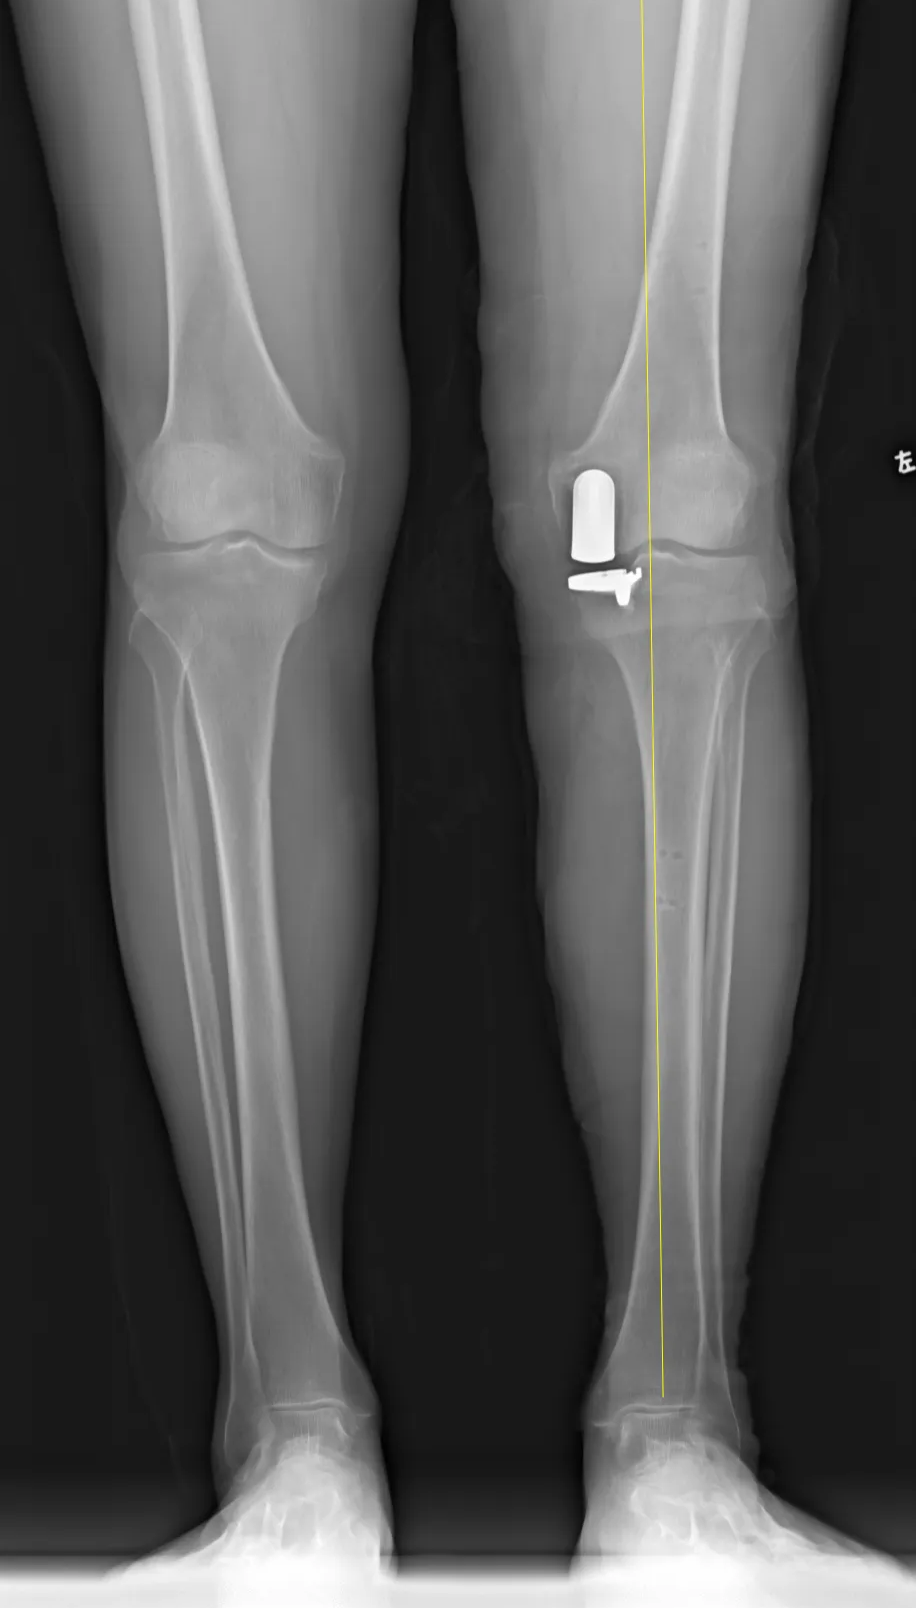

△术后假体位置极佳

目前,龙奶奶术后恢复良好,走路流畅,膝关节无外翻畸形,重拾了生活的希望。